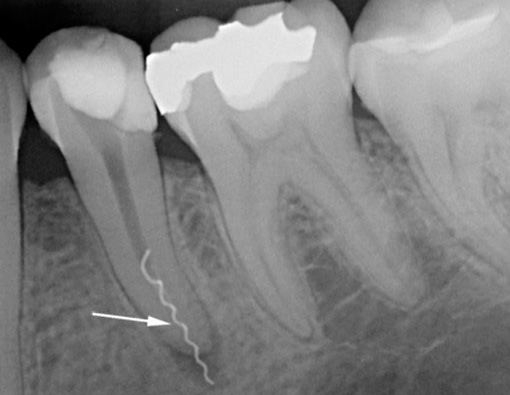

Un dente che è stato a lungo sigillato nei canali con un riempimento sigillato di alta qualità di solito non dà fastidio se non si sono verificati errori durante il trattamento. Se il vecchio sigillo cessa di soddisfare i requisiti di tenuta, o addirittura vola in pezzi, allora un dente morto inizia a ferire a causa dell'infezione nei canali già sigillati. Inoltre, durante il trattamento potrebbero essere commessi errori: un canale sigillato in modo incompleto con un'infezione rimasta al suo interno, uno strumento dentale rotto nel canale, ecc. Tutto ciò può anche causare infiammazione alla radice del dente e dolore nel tempo.

Le complicazioni durante e dopo il trattamento dei canali sono spesso provocate dal dentista a causa della scarsa formazione, mancanza di esperienza o attrezzature e materiali nella clinica. Molto spesso, il dolore dopo aver riempito i canali si verifica per i seguenti motivi:

- con eccessiva rimozione di materiale di riempimento oltre la radice;

- quando si salta un canale o canali in un dente;

- con scarsa elaborazione del canale;

- a causa di violazioni durante il passaggio e l'espansione di strumenti intra-canale;

- a causa del riempimento scadente;